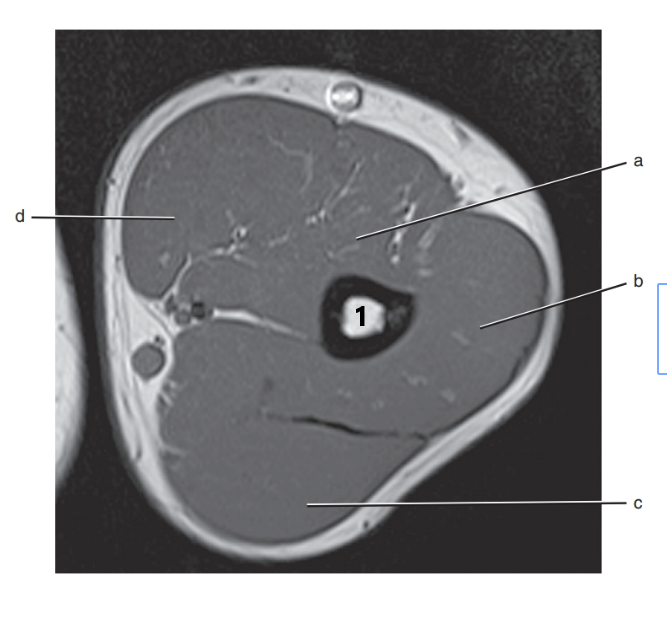

What is letter a?

Median nerve

Brachial artery

What is # 1 ?

humerus